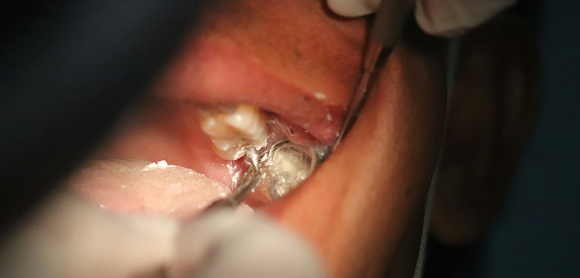

Auch wenn kein neues Amalgam mehr verwendet werden darf, bleibt die Entfernung bestehender Amalgamfüllungen weiterhin eine Aufgabe in Zahnarztpraxen. Hinzu kommen die Ausnahmen, in denen eine Amalgamfüllung noch medizinisch indiziert sein kann. Um Patienten, Ihr medizinisches Fachpersonal und sich selbst zu schützen, sind Schutzmaßnahmen für die Arbeit mit dem quecksilberhaltigen Material nötig.

• Verarbeiten Sie Amalgam nur mit Kofferdam, um Partikel im Behandlungsumfeld fernzuhalten.